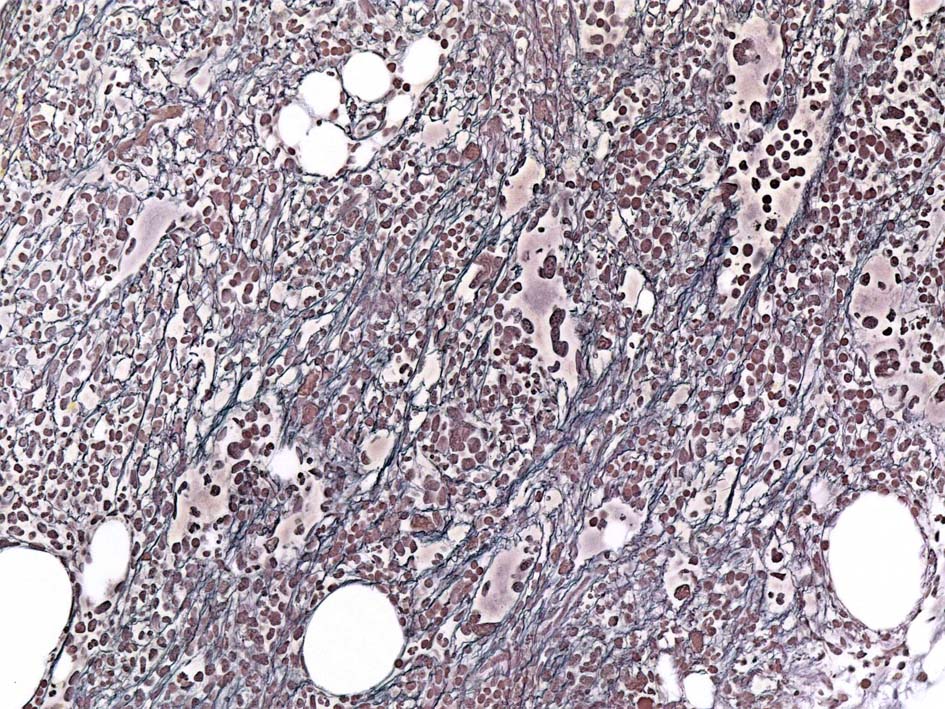

Case02; Meylofibrosis, overt fibrosis

77year-old female. 40歳時polycythemia veraと診断されていた.

黒染する弾性線維の増生のほか, 赤く染まる膠原線維の増生が確認される. MF-2 fibrosis. 鍍銀染色の核染色をすると膠原線維の赤染がわからなくなるので行わない.